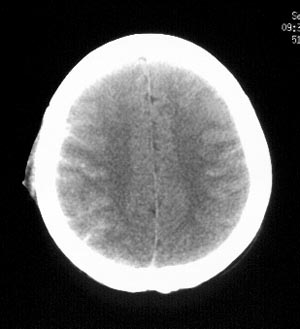

女性,36岁。头部外伤半小时,现觉头痛,有呕吐,无昏迷。

ct平扫:双侧脑沟、脑裂见密度增高,双侧大脑半球及颅后窝脑实质未见异常密度改变。

ct诊断:蛛网膜下腔出血。